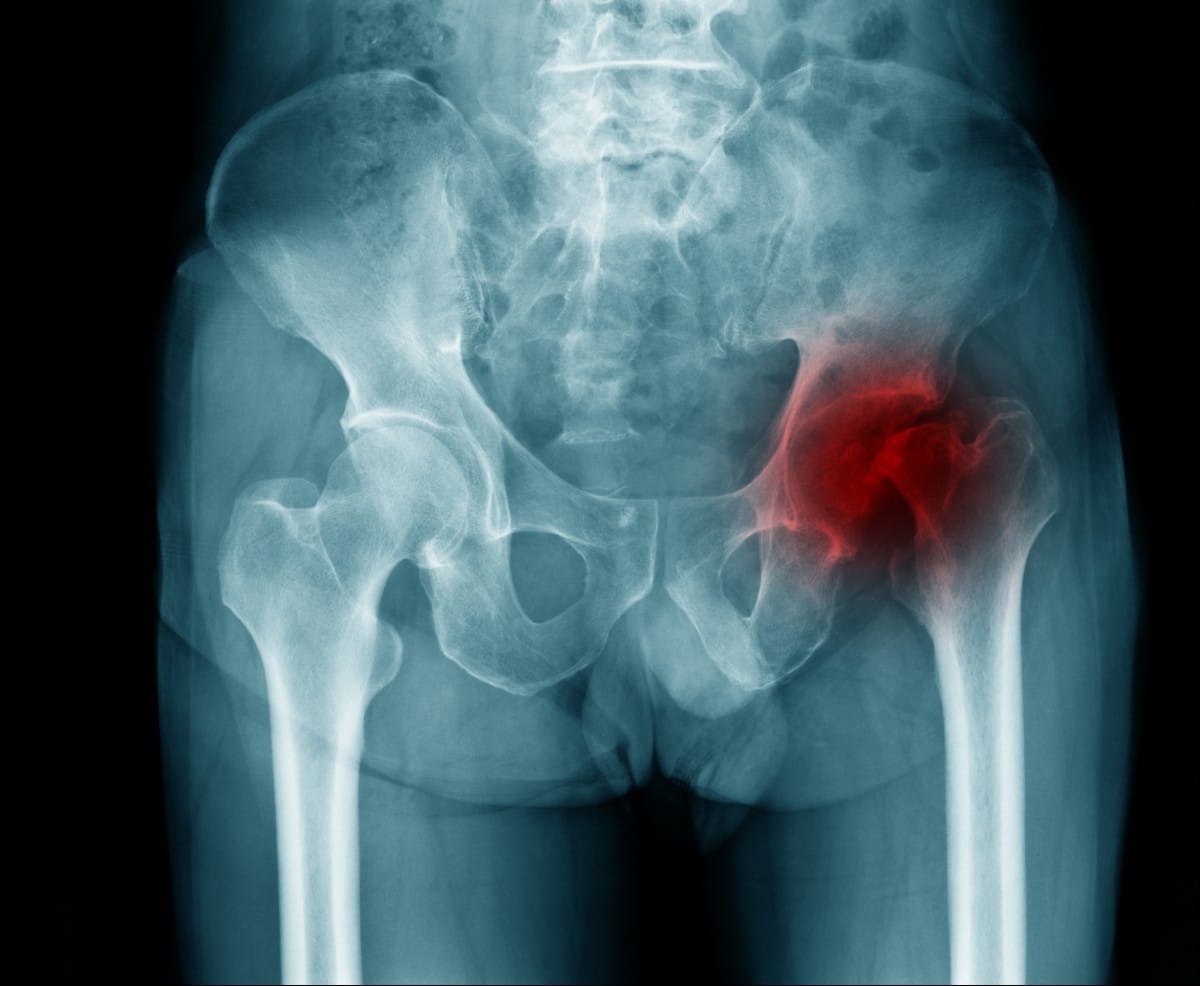

Osteoarthritis

Osteoarthritis, also known as “wear-and-tear” arthritis, is a common condition that mostly affects people aged 50 and older. It occurs when the protective cartilage at the ends of our bones wears down over time and can occur in any joint in the body. Since the hip is a weight-bearing joint, people are more susceptible to developing osteoarthritis there. Obesity, a family history of osteoarthritis, and a previous hip injury can also lead to an increased risk of developing hip osteoarthritis.

Osteoarthritis of the hip causes pain and stiffness in the hips and can make everyday activities such as walking or bending over difficult to carry out. While there can be a sudden onset of pain, it is more common for the pain caused by hip osteoarthritis to slowly worsen over time. For some people, this pain can also affect the knees or buttocks, or occur during vigorous activity. Occasionally, the hip may lock during movement, accompanied by a grinding noise which is caused by loose cartilage fragments. Some people also complain of greater pain in the morning, and in rainy or cold weather.